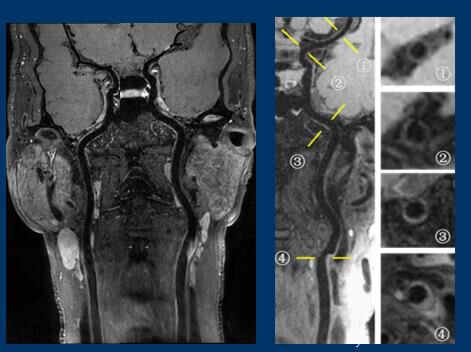

(左边是现有技术下的血管造影结果,白色为血管。右边是血管壁成像技术拍出的结果,黑色的为血管。)

“通过血管造影结果看这位病人的血管是没有什么问题的,但在血管壁成像下可以看到,颈动脉分岔的地方有一个斑块,白色高亮部分。调取横断面图像可以看到,病人斑块旁有一个缺口,脱落的斑块从缺口跑出来,形成血栓,堵塞血管。”